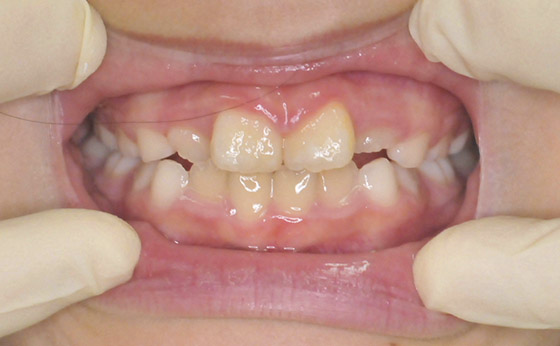

途中経過03

それから半年で永久歯に生え変わりましたが、前歯が開いてしまいました。

途中経過04

その後は簡単な矯正装置で修正、半年でここまで改善いたしました。